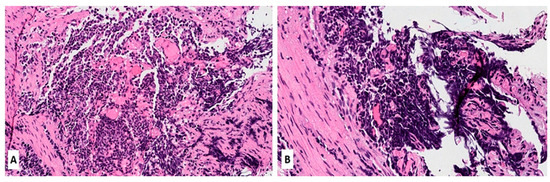

Morphologically, SCLC is composed of densely packed, small neoplastic cells with scanty cytoplasm and finely granular nuclear chromatin but without prominent nucleoli; nuclear molding and smudging are commonly present (Figure 1A,B). The cells are round or oval, although spindle cells (fusiform pattern of cancer cells) are frequently seen. Mitotic figures are numerous, while the tumor necrosis and crush artifacts may be extensive.

Figure 1.

(A,B) Hematoxylin and Eosin (H&E) stain of a lung biopsy showing a small cell carcinoma with sheet-like diffuse growth pattern and basophilic appearance (A, magnification 10×); Image 1B reveals a prominent nuclear molding of neoplastic cells (magnification 20×).